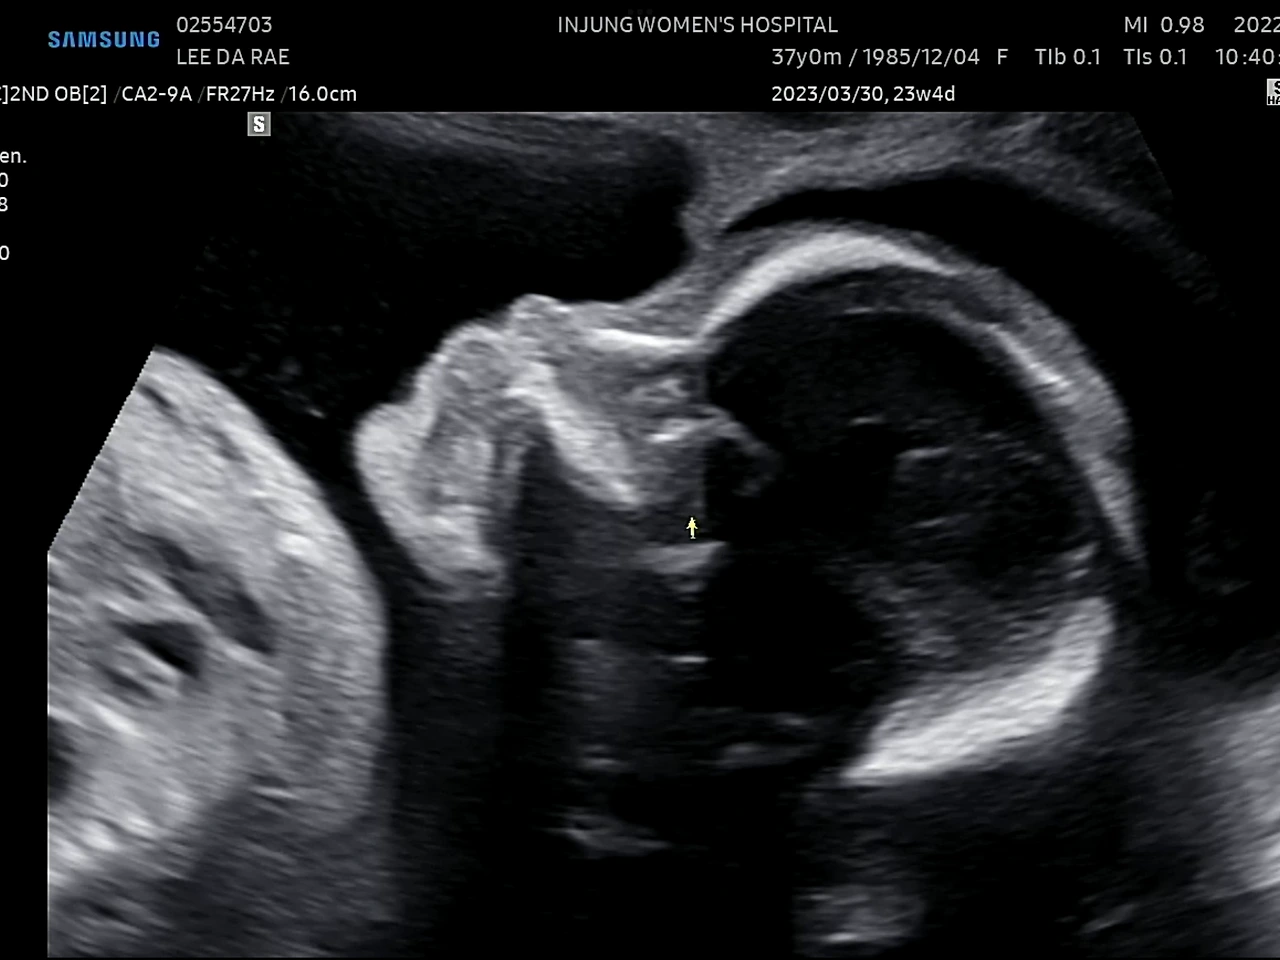

귀여운 얼굴

23주에 정밀초음파 검사를 받았다. 1차 기형아 검사에서 고위험군으로 나온 후로 모든 검사가 겁이 난다.(니프티검사에서 정상판정) 초음파 선생님(?)이 포도의 심장을 천천히 보시는데 한동안 아무 말씀도 없으시길래 너무 긴장이 됐다. 다행히 포도는 건강했다. 선생님이 아이가 쉬지 않고 움직인다고 하셨다. 아인이 때도 아이가 활발하다는 얘길 들었는데ㅋㅋ 남매라 그런가 비슷하네. 얼른 만나고 싶다 포도야!